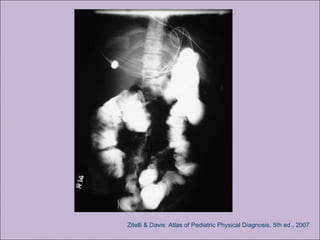

A) Intestinal: íleo meconial, síndrome da obstrução

intestinal distal, prolapso retal.

Doença gastro-intestinal e nutricionalDoença gastro-intestinal e nutricional

A) Intestinal: íleomeconial, síndrome da obstrução intestinal distal, prolapso retal. B) Pancreática: insuficiência pancreática, pancreatite recorrente. C) Hepática: doença hepática crônica D) Nutricional: hipodesenvolvimento pôndero-estatural , hipoproteinemia e edema, complicações secundárias à deficiência de vitaminas lipossolúveis. Doença gastro-intestinal e nutricionalDoença gastro-intestinal e nutricional Rosenstein. J Pediatr. 1998;132:389-95